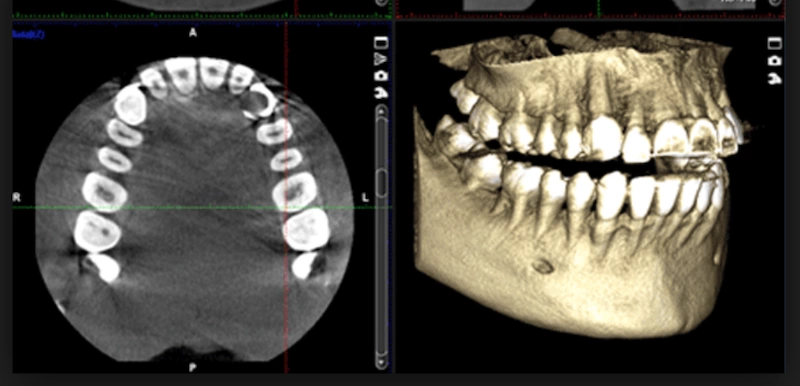

La cirugía convencional se basa en la experiencia directa del cirujano: la posición, el ángulo y la profundidad del implante se determinan intraoperatoriamente a partir de referencias anatómicas y radiológicas. La cirugía guiada, en cambio, utiliza un TAC 3D y un software de planificación digital para diseñar una férula que guía la perforación y colocación exacta del implante según el plan virtual.

La principal diferencia radica en la precisión y previsibilidad del resultado. Por un lado, en la cirugía guiada, todo el procedimiento se planifica antes de que el paciente entre en el quirófano: se estudia la anatomía ósea, se define el tamaño exacto del implante y se simula su posición final en relación con la futura prótesis. Esto permite anticipar posibles complicaciones, ajustar el plan del implante y ofrecer al paciente una visión clara del tratamiento postoperatorio antes de realizarlo.